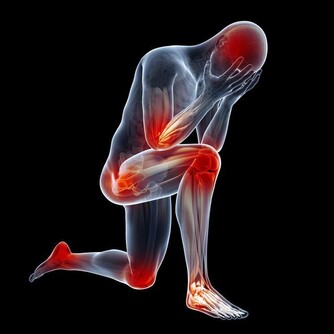

3. 肌肉:

30 歲後,肌肉的衰竭速度大於生成速度,到了40 歲更是以0.5-2% 的速度減少。